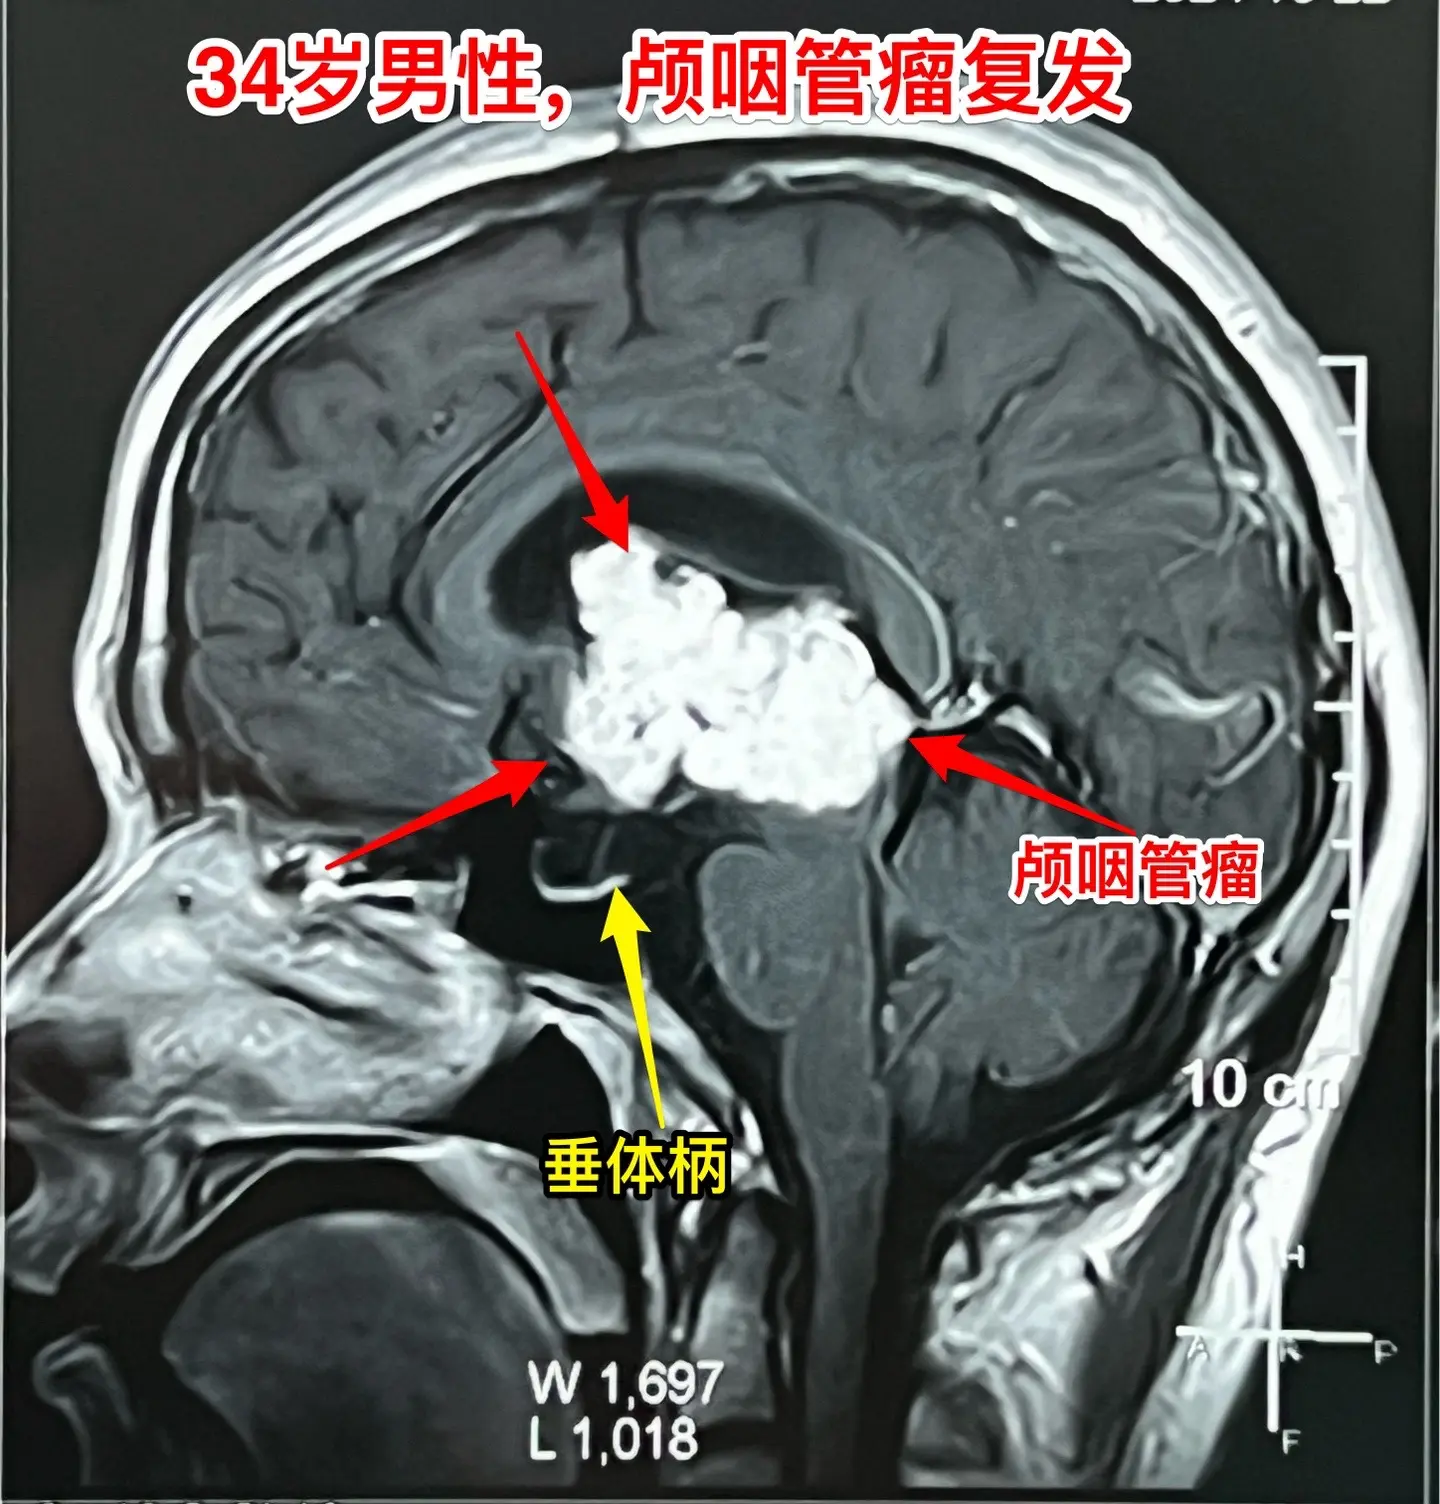

34岁广州男性颅咽管瘤复发。一年前他在广州市某医院行开颅手术切除颅咽管瘤,是乳头型颅咽管瘤。 今年发现肿瘤复发了,如图所示,可以见到肿瘤体积已经很大了!肿瘤主体位于第三脑室,部分肿瘤经室间孔进入侧脑室。 病人34岁了,未结婚。父母都不在了,两个姐姐和弟弟在照顾他。 第一次在外院手术是采用经侧脑室额角造瘘经室间孔入路切除颅咽管瘤的。 这个入路仍然适合现在的肿瘤,11月1日完成了手术,顺利切除肿瘤。颅咽管瘤乳头型颅咽管瘤